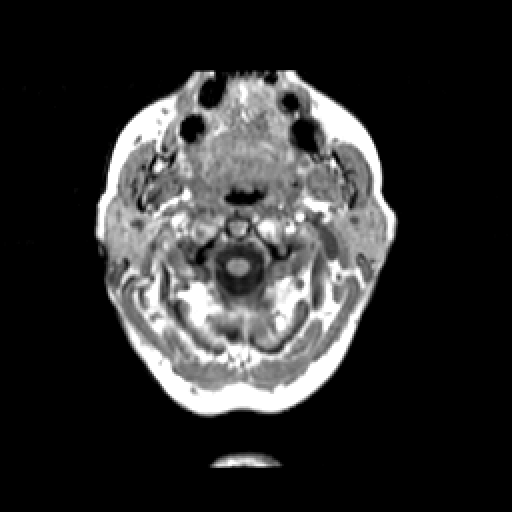

T1-weighted structural MR: Slice 1

Slice 1